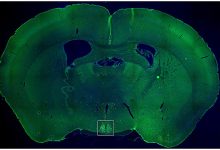

Usando modelos de ratos animais geneticamente modificados para terem progéria, a equipe de pesquisa conseguiu mostrar problemas cardíacos precoces, como os observados em crianças com a doença. A equipe descobriu que uma única injeção do gene da longevidade ajudou a melhorar a função cardíaca, especificamente como o coração relaxa e se enche de sangue – chamada função diastólica.

Reduziu os danos ao tecido cardíaco – chamados fibrose – e diminuiu o número de células “envelhecidas” no coração. O gene também impulsionou o crescimento de novos pequenos vasos sanguíneos, o que poderia ajudar a manter o tecido cardíaco saudável.